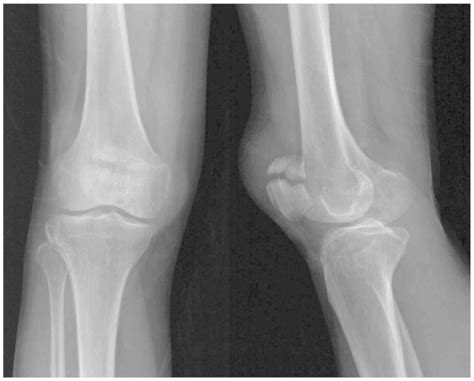

During the typical development of a human skeleton, the patella begins as multiple centers of ossification (bone formation). Usually, these centers fuse together during early adolescence to form one solid, singular bone. In individuals with a Bi Part Patella, this fusion process fails to occur completely, leaving a small accessory bone—most commonly located at the upper outer corner of the kneecap—separated from the main body of the patella.

⚠️ Note: It is critical to differentiate between a symptomatic bipartite patella and a recent patellar fracture. Unlike a fracture caused by sudden trauma, a bipartite patella typically features smooth, rounded edges on the separated bone fragments, which can be clearly visualized on X-rays.

Diagnosis usually begins with a thorough physical examination, during which a healthcare professional will press on the kneecap to locate the exact point of tenderness. To confirm the diagnosis and rule out other potential causes of knee pain, imaging studies are essential:

X-Ray The primary tool to visualize the separation in the bone.